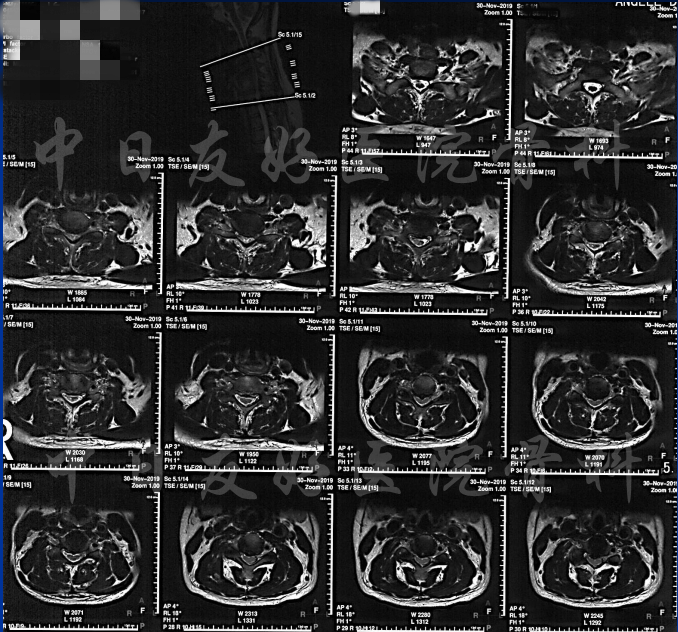

颈CT(上下滑动)

腰椎MRI

诊断:

OPLL--颈椎、颈椎管狭窄、颈椎后凸、颈椎术后、腰椎管狭窄、行走困难、肢体麻木、高血压、 糖尿病、 高脂血症、陈旧性脑梗塞、 慢性胃炎。